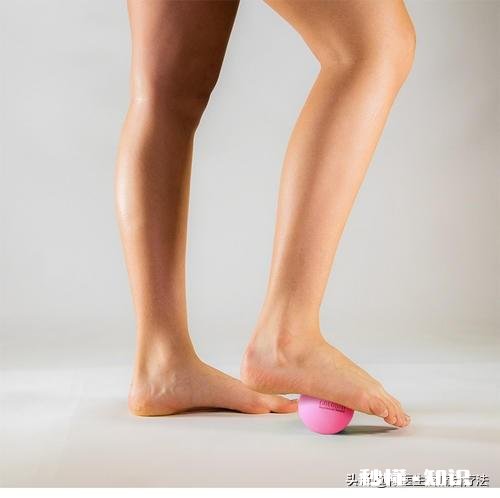

5.踩网球

在脚部从前往后进行按摩,注意用力按压到每一个部位,中间和边缘都要按摩到,并在按压区域停留15秒作用 。

文章插图

治疗出现足跟疼痛以后,首先检查小腿及足底的肌肉是否存在压痛点,因为这是足跟痛最常见的原因 。小腿后面的压痛点可以用对侧的膝盖按摩,将患侧的小腿放在对侧的膝盖上,对准痛点移动小腿按摩 。每个痛点按摩两分钟每天三次 。足底的压痛点可以采用筋膜球按摩,把筋膜球放在脚下对准痛点滚动按摩 。

一般来讲,你这种表现很像足底筋膜炎,由于每个人生活环境不一样,还有的人扁平足,造成这个问题的概率会增高,可以在足底触诊一下,用手按不方便,还是自己踩按摩球找一下痛点,如果有明显的疼痛,早晨起来痛的那只脚远痛于另一侧,可确诊!

自我按摩

文章插图

对于身体的这种小疼痛,可以自我按摩来消除症状,平时没事的时候,可以用脚踩按摩球(高尔夫球、网球),以疼痛感觉舒服的力度按摩,每次5~7分钟,踩完就会感觉到舒服,坚持一周看是否会好转,好转就坚持到痛点消失!